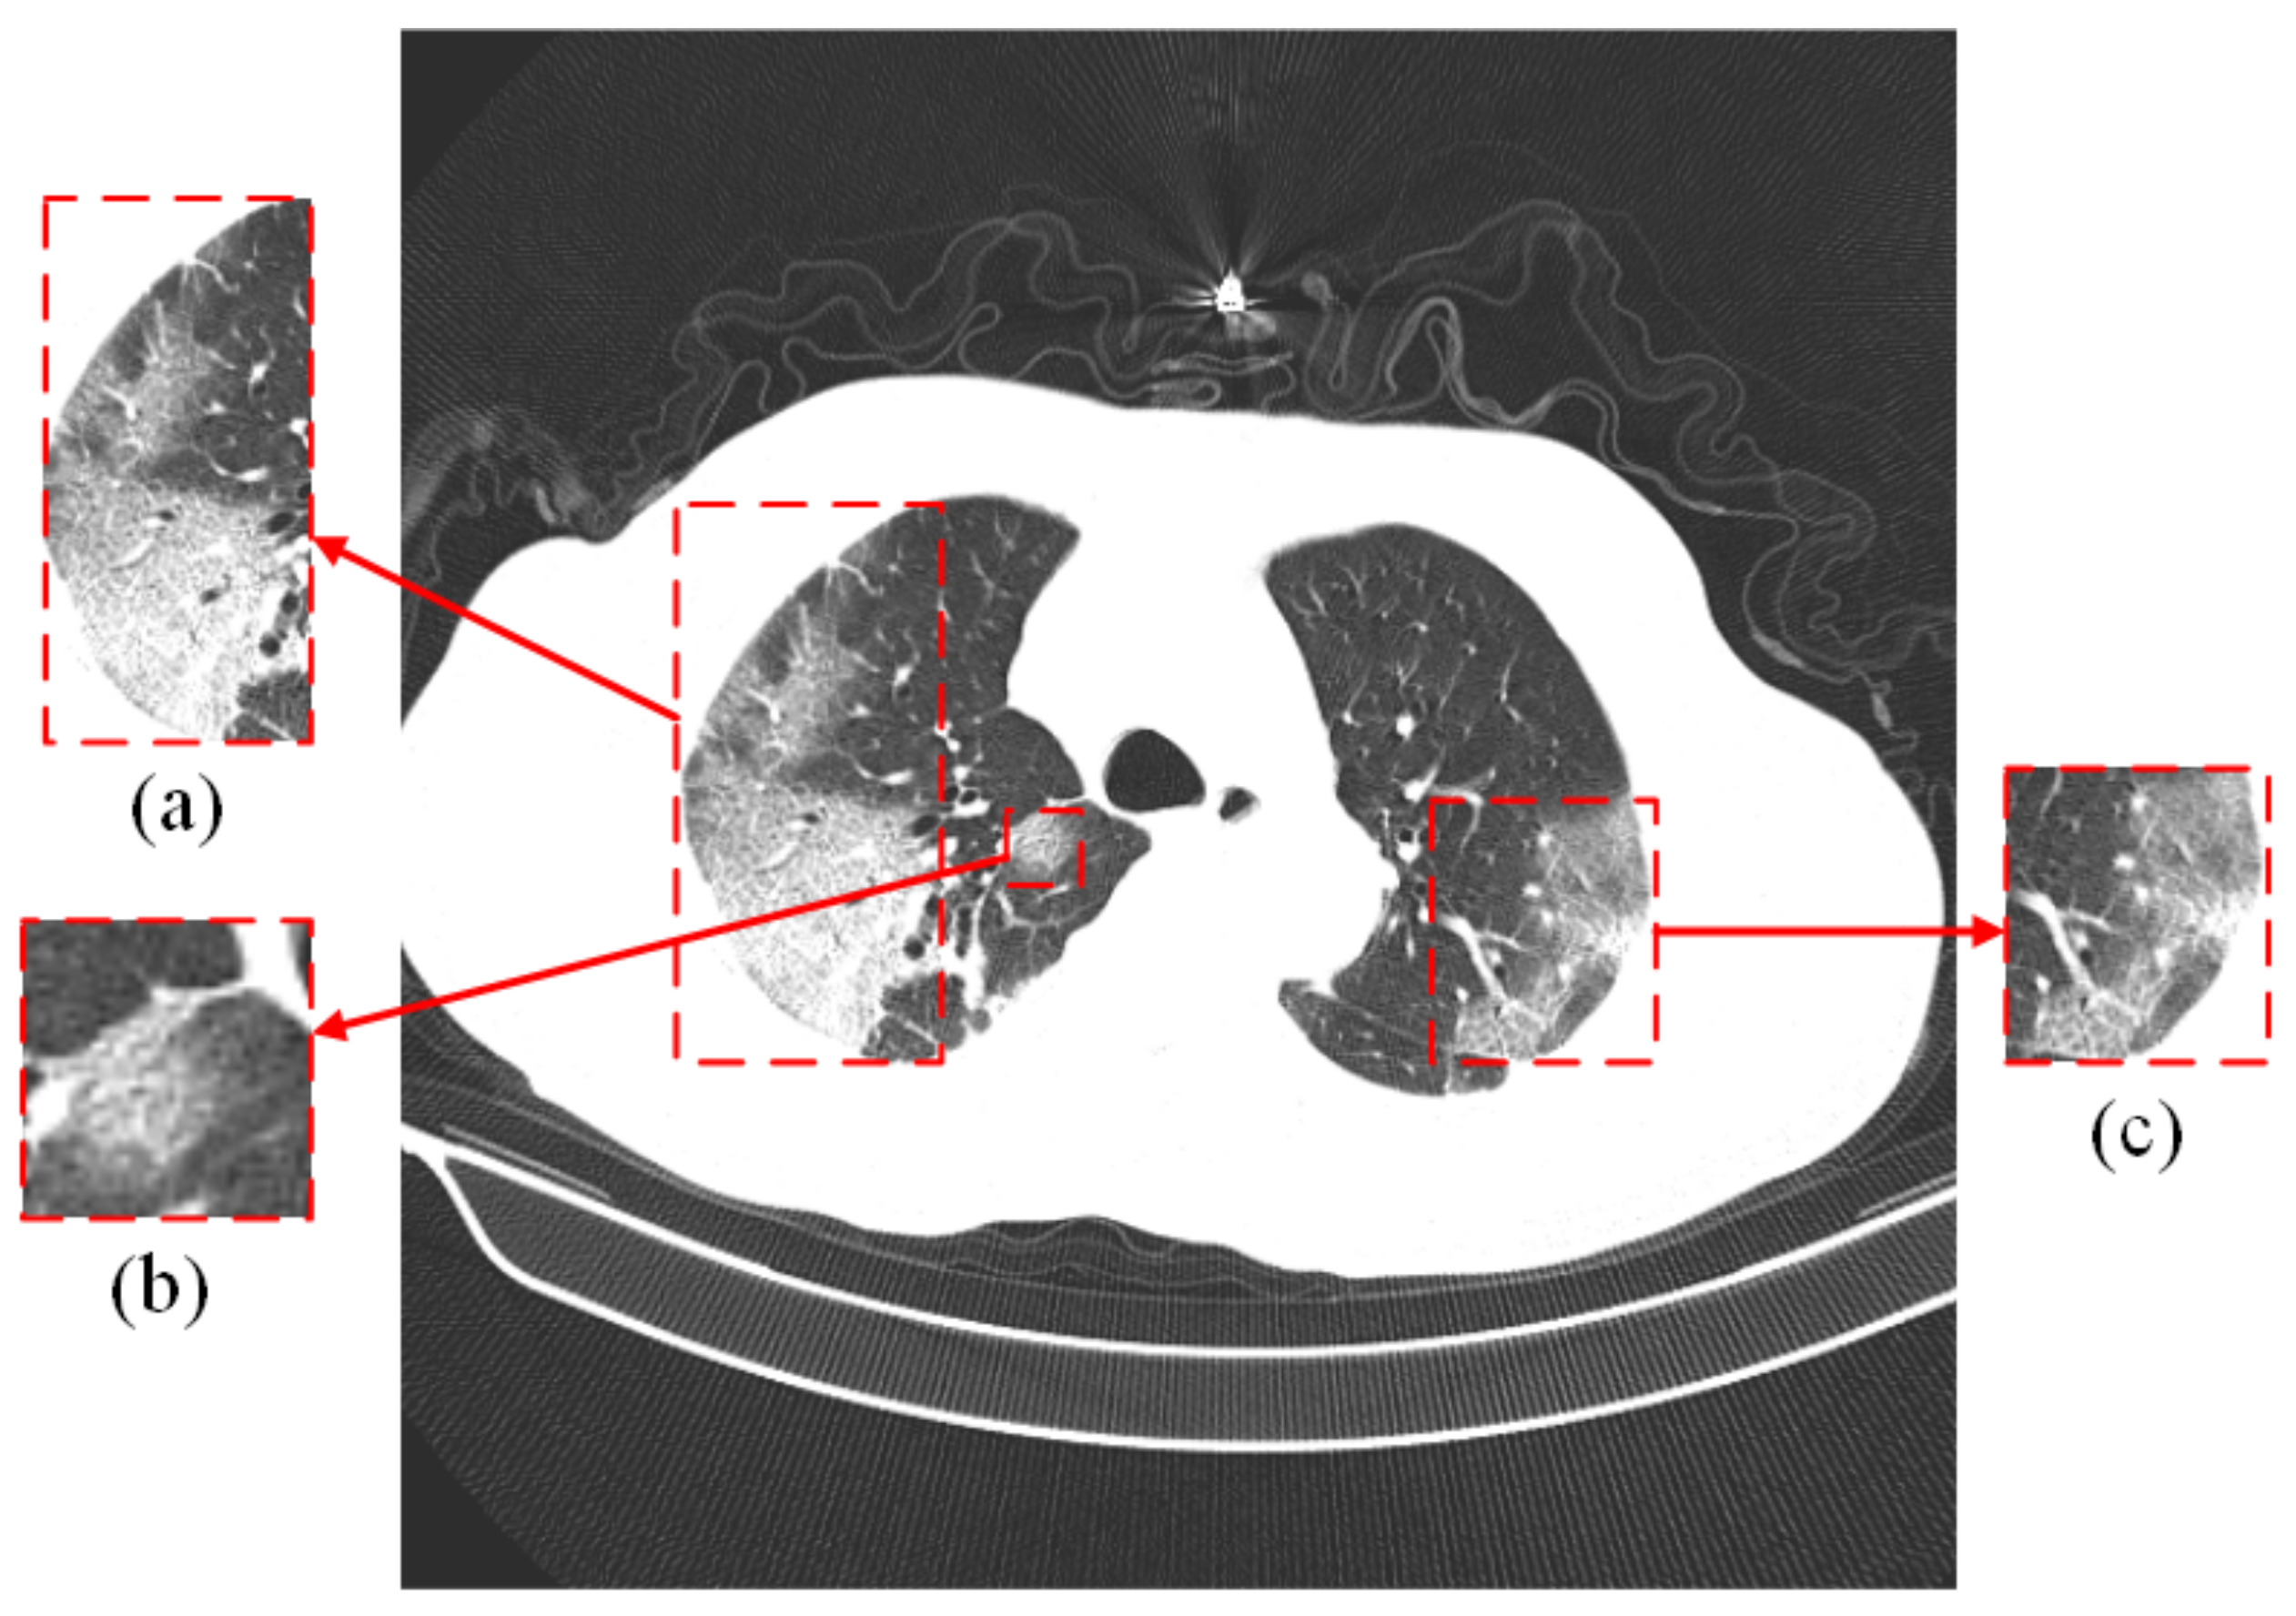

The most commonly used method for detecting SARS-CoV-2 is real-time reverse transcription polymerase chain reaction (RT-PCR). It is regarded as the gold standard for the diagnosis of SARS-CoV-2 due to its high sensitivity and high specificity [4,5], which is achieved by collecting samples from the upper respiratory tract (e.g., nasopharynx or oropharynx). However, this method is time-consuming and requires medical personnel with specialized skills, as well as a specific laboratory [6]. In addition, the RT-PCR method depends on the collected samples, and if the samples are not collected, transported, and stored appropriately, it could lead to false-negative results [7,8]. Another way to detect the disease is by computed tomography (CT) and X-ray, which is achieved by consolidation or ground glass opacity (GGO) in the lungs [9], as indicated by the red rectangular box in Figure 1. While both can be used for the diagnosis of COVID-19, chest CT images can show detailed information about the infected area. Some researchers found that the 98% sensitivity of chest CT is higher than the 71% sensitivity of RT-PCR by comparing CT images and RT-PCR tests at the initial patient visit [10]. This indicates that CT images of the lungs are more useful for the early diagnosis of patients.

Figure 1.

The lung CT image of a COVID-19 patient. (a–c) are ground glass images. The original image comes from the COVIDx CT-2A dataset [11,12].